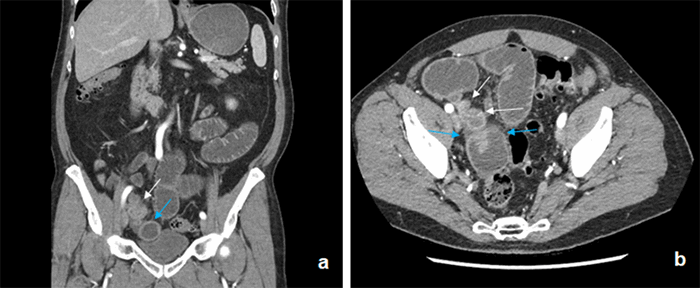

The patient, a 70-year-old male, presented to the ED four times over a one-month period for intermittent periumbilical abdominal pain. His past surgical history was notable for cholecystectomy and prostatectomy for nonmetastatic prostate cancer. CT imaging on his first and third admission showed a SBO with a transition point in the right lower quadrant (RLQ) (Figure 1). Of note, no radiographic abnormalities of the appendix were identified on the official radiology reports. Additionally, he had an upper GI series with small bowel follow through that showed dilated loops of small bowel filled with contrast and small amounts of contrast in the large bowel, consistent with a high-grade partial SBO. The patient’s first three admissions for SBO were self-resolving, and he was managed nonoperatively. On his fourth presentation, the decision was to made to perform an exploratory laparoscopy.

Figure 1. CT abdomen pelvis performed during admission for SBO. (A) Coronal slice. (B) Axial slice. The distal appendix (white arrows) is markedly dilated and adherent to the distal ileum (blue arrows). Significant dilation of the small bowel can be seen proximal to the RLQ transition point.